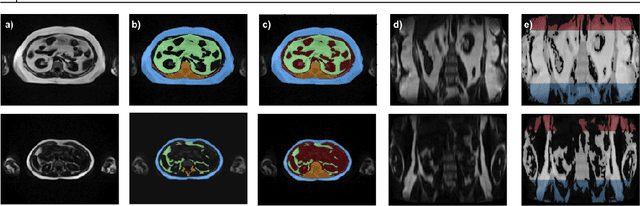

Abstract:Purpose: Development of a fast and fully automated deep learning pipeline (FatSegNet) to accurately identify, segment, and quantify abdominal adipose tissue on Dixon MRI from the Rhineland Study - a large prospective population-based study. Method: FatSegNet is composed of three stages: (i) consistent localization of the abdominal region using two 2D-Competitive Dense Fully Convolutional Networks (CDFNet), (ii) segmentation of adipose tissue on three views by independent CDFNets, and (iii) view aggregation. FatSegNet is trained with 33 manually annotated subjects, and validated by: 1) comparison of segmentation accuracy against a testingset covering a wide range of body mass index (BMI), 2) test-retest reliability, and 3) robustness in a large cohort study. Results: The CDFNet demonstrates increased robustness compared to traditional deep learning networks. FatSegNet dice score outperforms manual raters on the abdominal visceral adipose tissue (VAT, 0.828 vs. 0.788), and produces comparable results on subcutaneous adipose tissue (SAT, 0.973 vs. 0.982). The pipeline has very small test-retest absolute percentage difference and excellent agreement between scan sessions (VAT: APD = 2.957%, ICC=0.998 and SAT: APD= 3.254%, ICC=0.996). Conclusion: FatSegNet can reliably analyze a 3D Dixon MRI in1 min. It generalizes well to different body shapes, sensitively replicates known VAT and SAT volume effects in a large cohort study, and permits localized analysis of fat compartments.

Abstract:Increased information sharing through short and long-range skip connections between layers in fully convolutional networks have demonstrated significant improvement in performance for semantic segmentation. In this paper, we propose Competitive Dense Fully Convolutional Networks (CDFNet) by introducing competitive maxout activations in place of naive feature concatenation for inducing competition amongst layers. Within CDFNet, we propose two architectural contributions, namely competitive dense block (CDB) and competitive unpooling block (CUB) to induce competition at local and global scales for short and long-range skip connections respectively. This extension is demonstrated to boost learning of specialized sub-networks targeted at segmenting specific anatomies, which in turn eases the training of complex tasks. We present the proof-of-concept on the challenging task of whole body segmentation in the publicly available VISCERAL benchmark and demonstrate improved performance over multiple learning and registration based state-of-the-art methods.